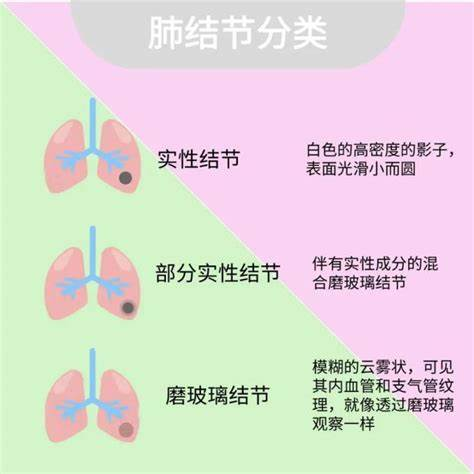

肺结节并不是一种特定的疾病,而是影像学上的一个描述性名词。简单来说,就是做检查时在肺部发现的一个圆形或类圆形的小的异常阴影,直径通常小于3cm。肺结节可以单个的,也可以是多个的。根据CT检查中的结节密度,肺结节可分为实性结节和磨玻璃结节,其中磨玻璃结节又可分为纯磨玻璃结节和混合磨玻璃结节。